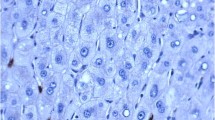

To observe whether TNF-α promotes lymph node metastasis through upregulation of CCR7 in vivo, we established two orthotropic xenograft models by planting NOZ and LV-shCCR7 cells in the gallbladder of nude mice (Fig. 6a). After 2 weeks, TNF-α or normal saline was injected into the peritoneal cavity of nude mice three times a week for three weeks. Lymph node metastases (LNM) of GBC were observed with the naked eye (Fig. 6c) and confirmed by HE staining (Fig. 6d). As shown in Table 5, TNF-α increased the LNM of orthotropic xenograft tumours compared to the control group, and this effect was impaired when the CCR7 was knocked down by lentiviral-mediated shRNA (LV-shCCR7 group). We also observed ascites and hepatic metastases in some mice (Fig. 6b).

Fig. 6 The TNF-α-CCR7 axis is involved in lymph node metastasis of GBC in vivo. a Establishment of orthotopic xenograft models of GBC in nude mice. After anaesthesia and exposure of the gallbladder (black arrow), one of two NOZ cell lines (NOZ or LV-shCCR7) was injected into the cavity of the gallbladder. b-c Gross anatomy of the nude mice. Ascites (green arrow) and hepatic metastasis (white arrow) were observed in the orthotopic xenograft models (b). The metastatic lymph nodes (blue arrow) are mainly located in the hepatoduodenal ligament (c). d Lymph node metastasis was further confirmed by H-E staining (200×). The invasive tumour cells (yellow arrow) could be observed in the lymphoid follicles (red arrow)